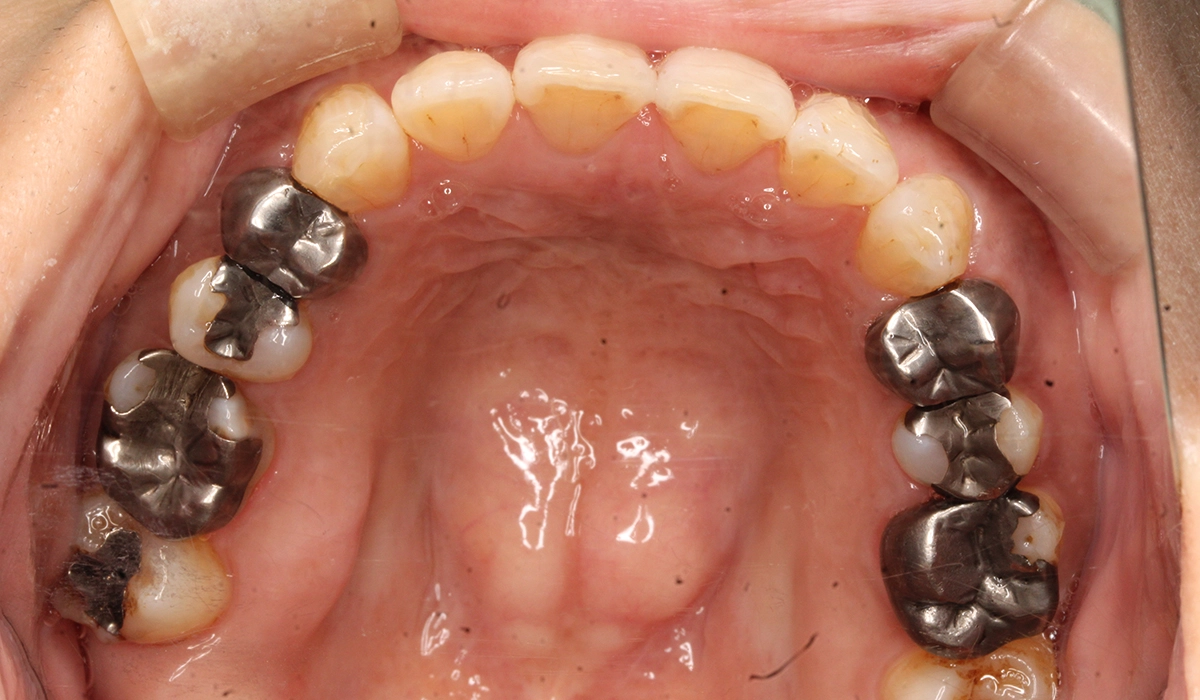

術前:上顎